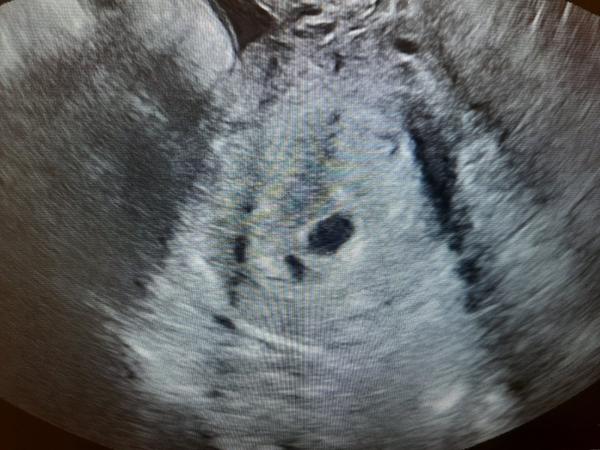

Prázdny vačok v 6. týždni

Ahojte. Dnes som bola u gynekologa, podla vsetkwho som dnes presne 6tt, 2 tyzdnove meskanie MS. na ultrazvuku videl 1cm vačok ktory je ale prazdny. Mam sa vratit za 10 dni. Pid tym vacsim vackom mam jeden mensi, k tomu mi nevedel povedat nic, ze mozno len nejaka mensia cysta alebo nevie co to moze byt ale ze to nemam riesit. Prikladam fotky utz.. je to podla vas ok, ze tam este nie je vidno mimi? som z toho smutna.😣